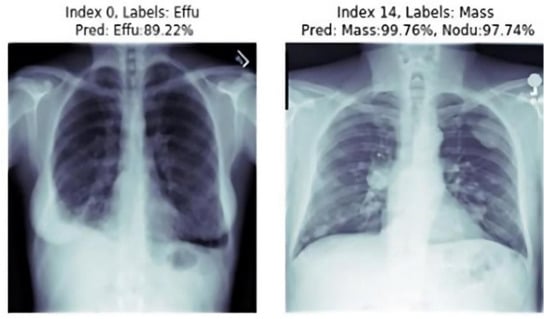

As we can see in the image with the index zero from Figure 9, the ground truth label was “Effusion”. Knowing that the model had AUC 0.89, the result was not surprising in that it gets 89.22% as a prediction. For the second image, we can see that the model starts getting a compromise and that the true diseases in this picture was “Mass”, and the prediction of the models of two diseases got a prediction rate higher than 97%.

Figure 11. Result of the prediction attempt from the testing set: two other samples with different index labels. Each one could have one or more diseases.